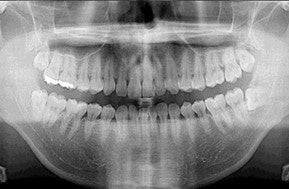

2. パノラマレントゲン検査

パノラマレントゲン検査パノラマレントゲン検査

パノラマレントゲンで撮影を行い、虫歯や歯周病の状態を詳細に把握し、ご説明いたします。

※ご希望の方には特別価格、別途5,500円(税込)でCT撮影を行います。